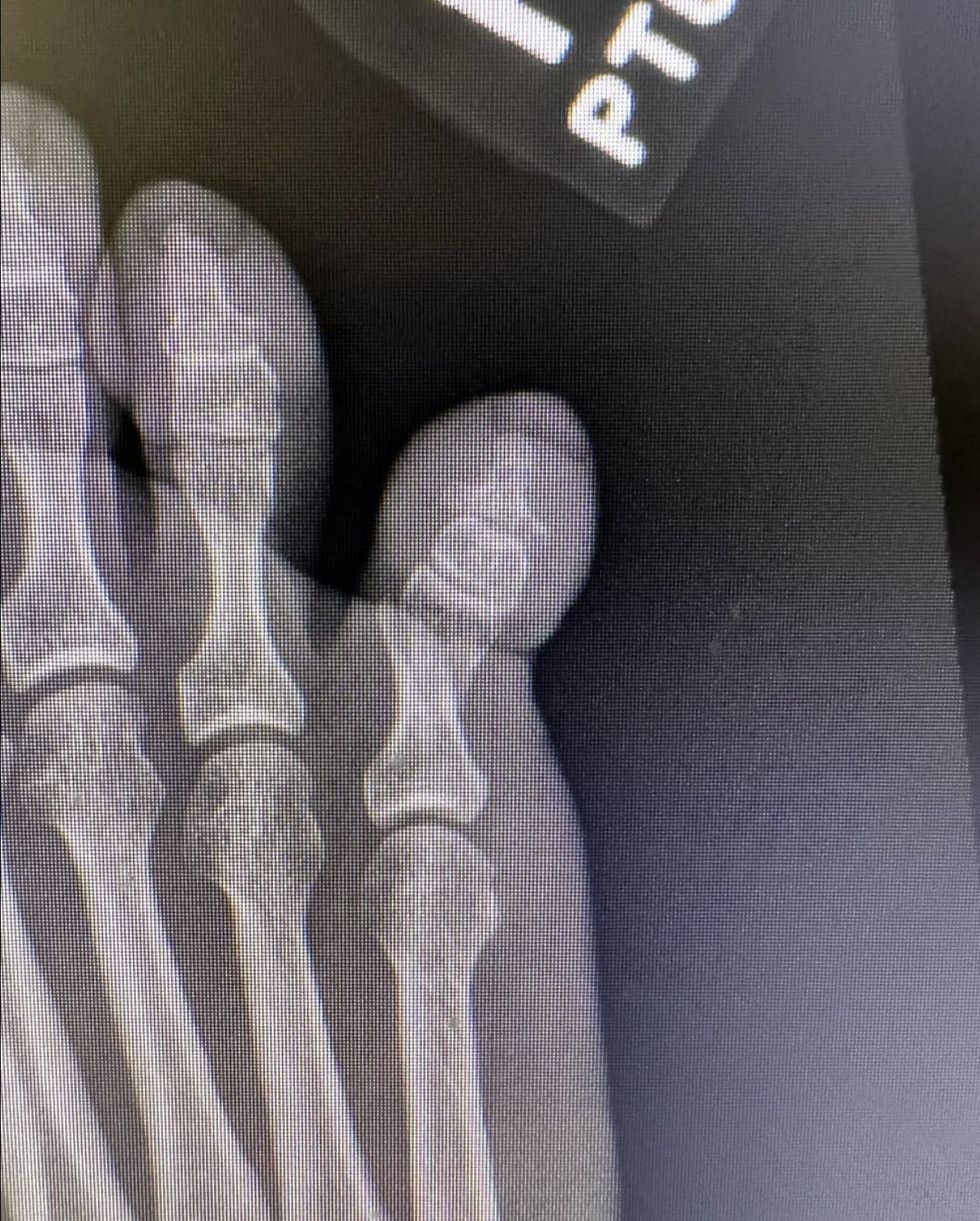

Norwegian Hovland, ranked eighth in the world, shared an X-ray on social media revealing what appears to be a broken toe after an unfortunate encounter with his bed frame.

Hovland broke the news of his unusual injury on Instagram last Friday, sharing an X-ray image of what appears to be his fractured right pinky toe.

The 27-year-old golfer humorously captioned the post: "Bed frame 1 - 0 me."

Viktor Hovland suffered a broken toe after kicking his bedframe by accident